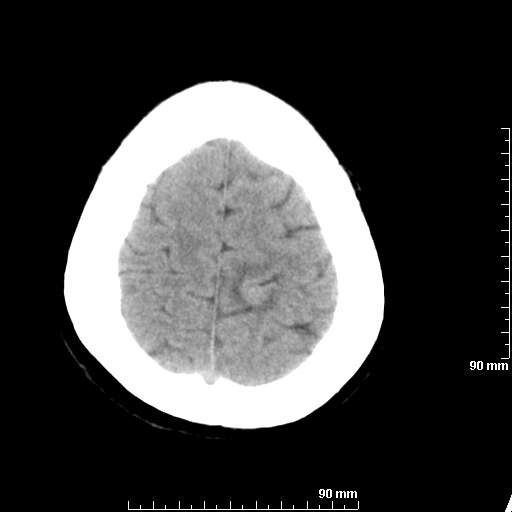

[维修案例解析] 大家猜猜看,这个伪影是怎样产生的.

我院西门子单排CT由于一零件受损而产生的伪影.

哈哈,都不是。是虑线器fiter裂损。大家没想到吧。

哦,跟脑出血有点像哦

形状不规则,边缘模糊。比较特殊的一种伪影哈!

这种伪影很常见!伪影应该是在视野的中心的。

西门子的虑线器fiter裂损这才是很难见的问题,GE的最常见

虑线器老化,中间崩裂一块掉了